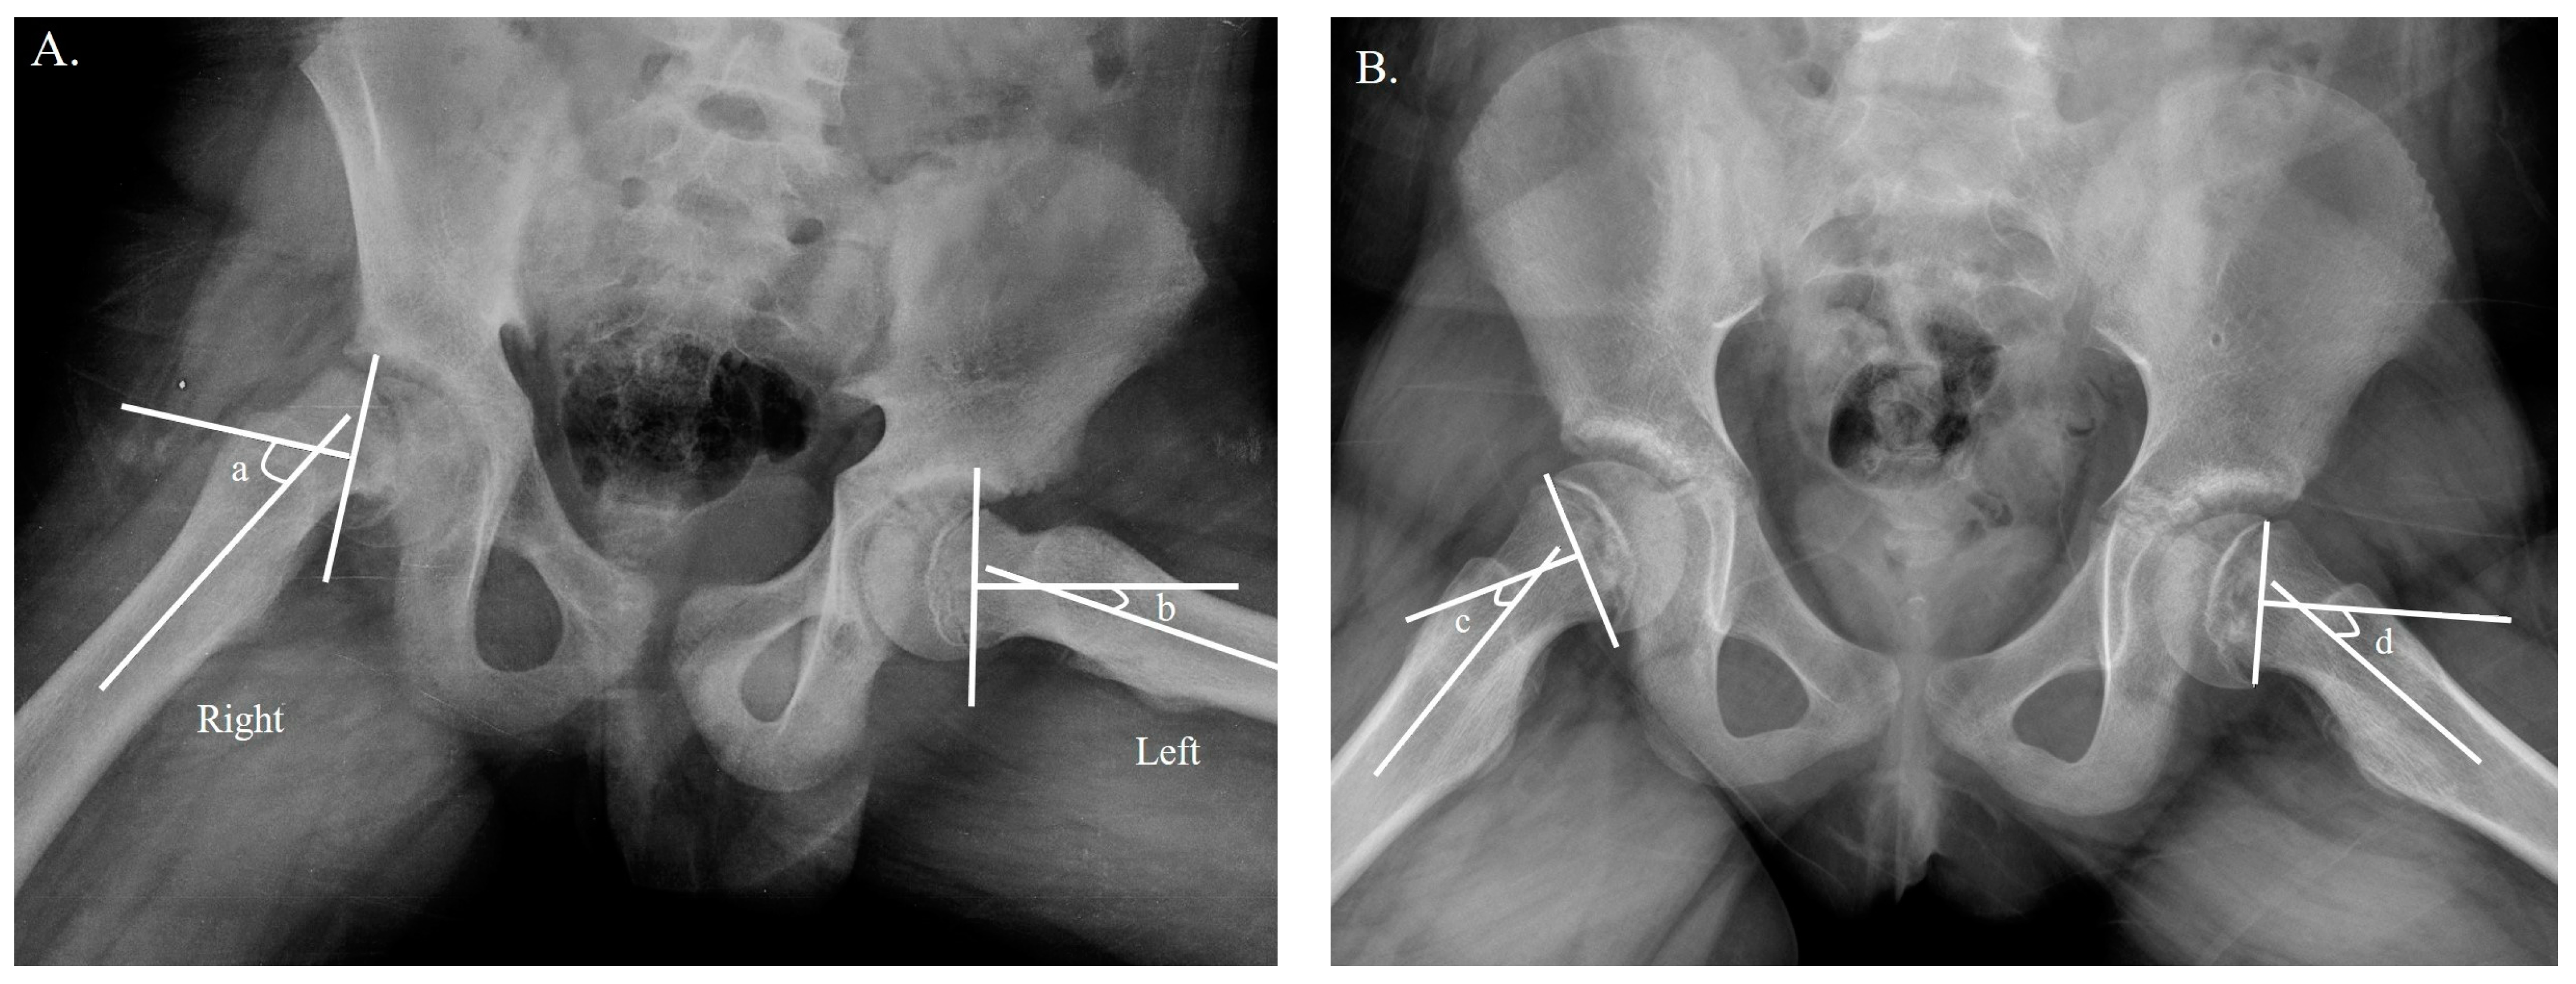

- Southwick, W.O. Osteotomy through the lesser trochanter for slipped capital femoral epiphysis. JBJS 1967, 49, 807–835. [Google Scholar] [CrossRef]